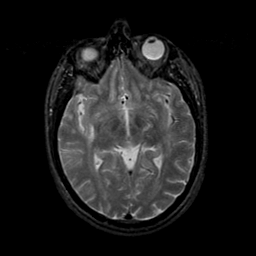

MR Study #9, April 14, 1991 -- Slice #23